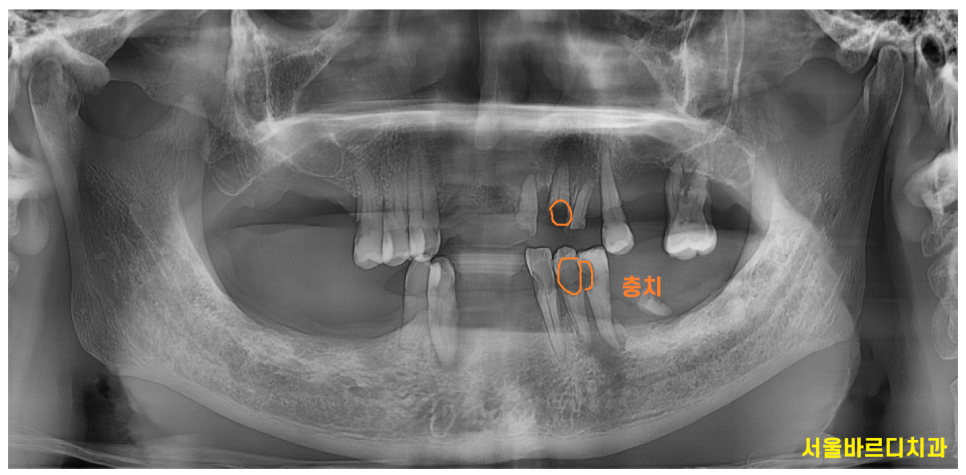

240423

전반적으로 치아가 망가진 경우

치아의 높이 역시 무너진 경우가 많습니다.

오늘 환자분도 씹는 부위가 딱 1부분이었습니다.

240513

뿌리만 남은 치아

충치가 심한 곳들

잇몸이 안좋아 흔들리는 부분

정리할 치아들은 발치 후